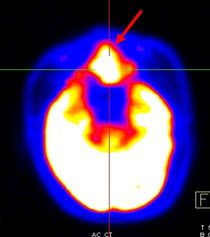

Hình 2. Bệnh nhân Trần V. V., nam, 57 tuổi. Chẩn đoán: u lympho hốc mũi; Giải phẫu bệnh: WF5. Hình CT, PET và PET/CT cho thấy tổn thương u ở vùng hốc mũi trái (mũi tên) tăng hấp thu FDG.

Hình 3. Bệnh nhân Lê V.T., nam, 73 tuổi. Chẩn đoán: U lympho ác tính không Hodgkin biểu hiện ở màng cứng ống tủy sống. Hình PET/CT cho thấy tổn thương tăng hấp thu FDG tại ống tuỷ sống (hình ovan).